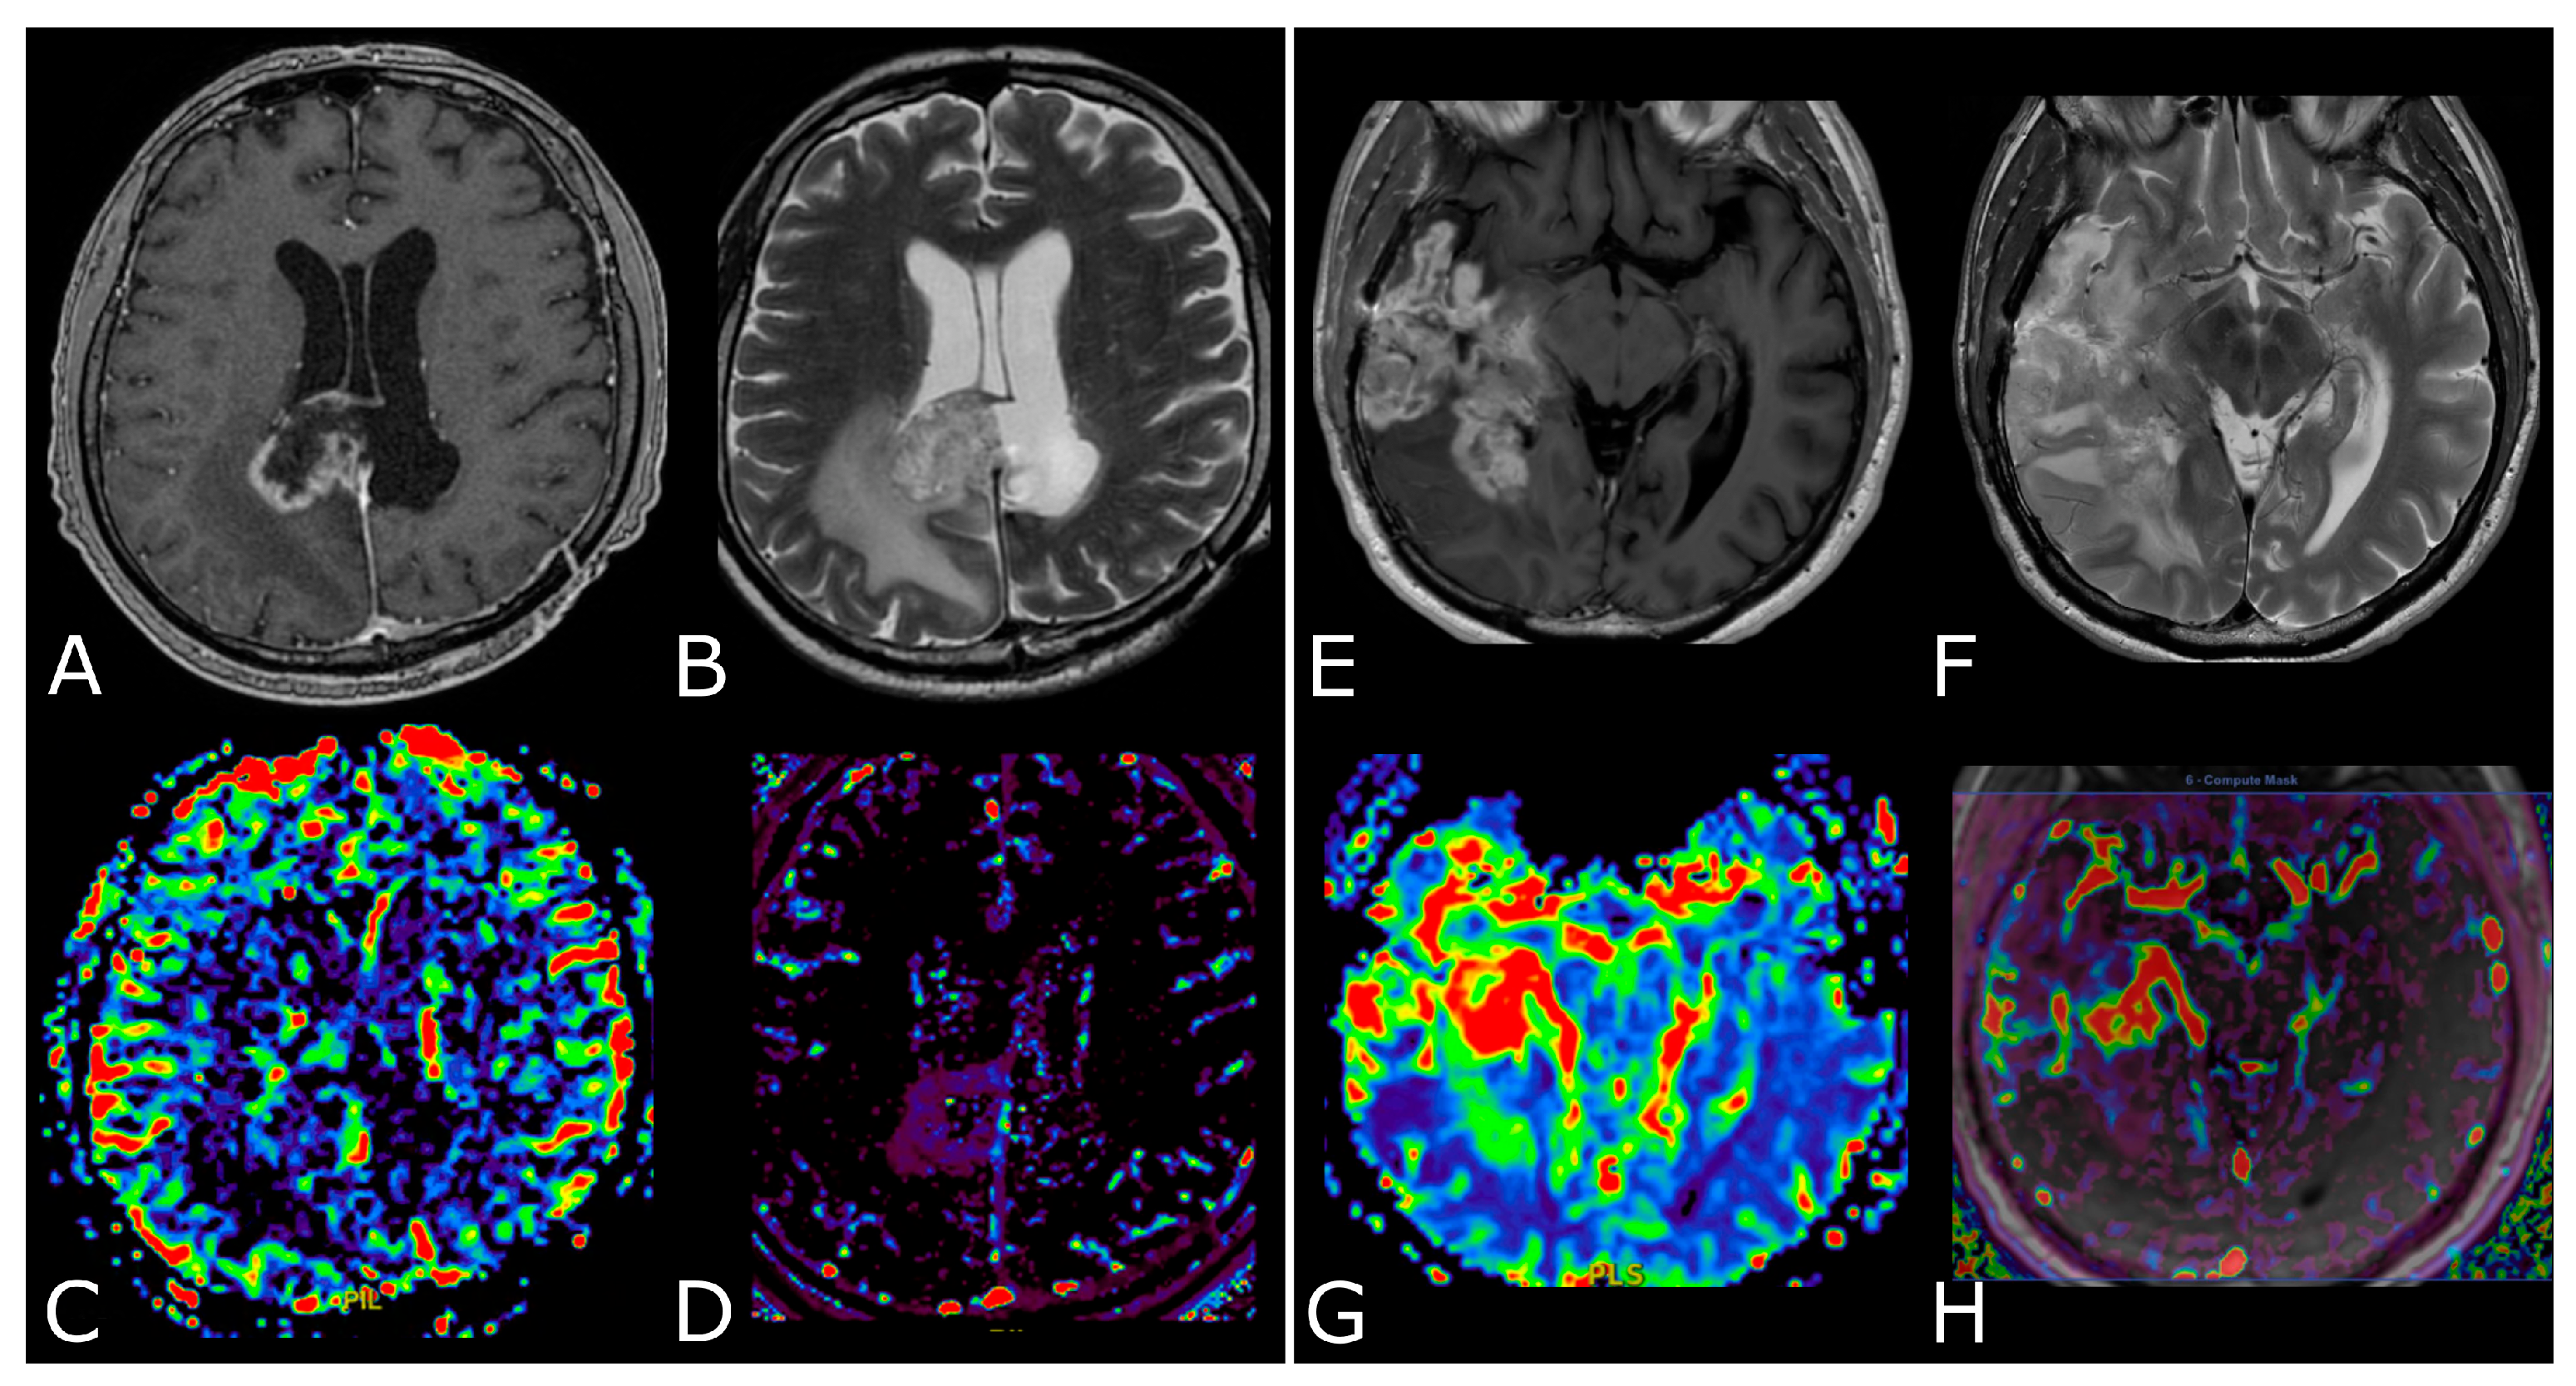

Figure 4.

DSC-PWI in differentiating HGG from LGG. Axial T2-FLAIR (A) and post-contrast T1w (B) of a low grade IDH-mut left insular astrocytoma. DSC-PWI demonstrates normal rCBV (C) and complete return to baseline of the signal-intensity-time curve (D). The second row shows axial T2-FLAIR (E) and post-contrast T1w (F) of a left temporal-occipital GB. DSC-PWI demonstrates increased rCBV (G) and reduction of PSR consistent with BBB breakdown (H).

Figure 5.

Post-treatment changes vs. disease progression. (A–H): axial 3D-FSPGR post-contrast T1w images (A,E) and T2w images (B,F) with corresponding DSC-CBV (C,D) and DCE-Ktrans perfusion maps (G,H) of two IDHwt GBs 1 year after treatment (surgery and radio-chemotherapy). In the left panel the enhancing tissue shows low DSC-CBV and DCE-Ktrans, consistent with post-treatment changes. In right panel the enhancing tissue shows areas of increased DSC-CBV and DCE-Ktrans, suggesting disease progression.